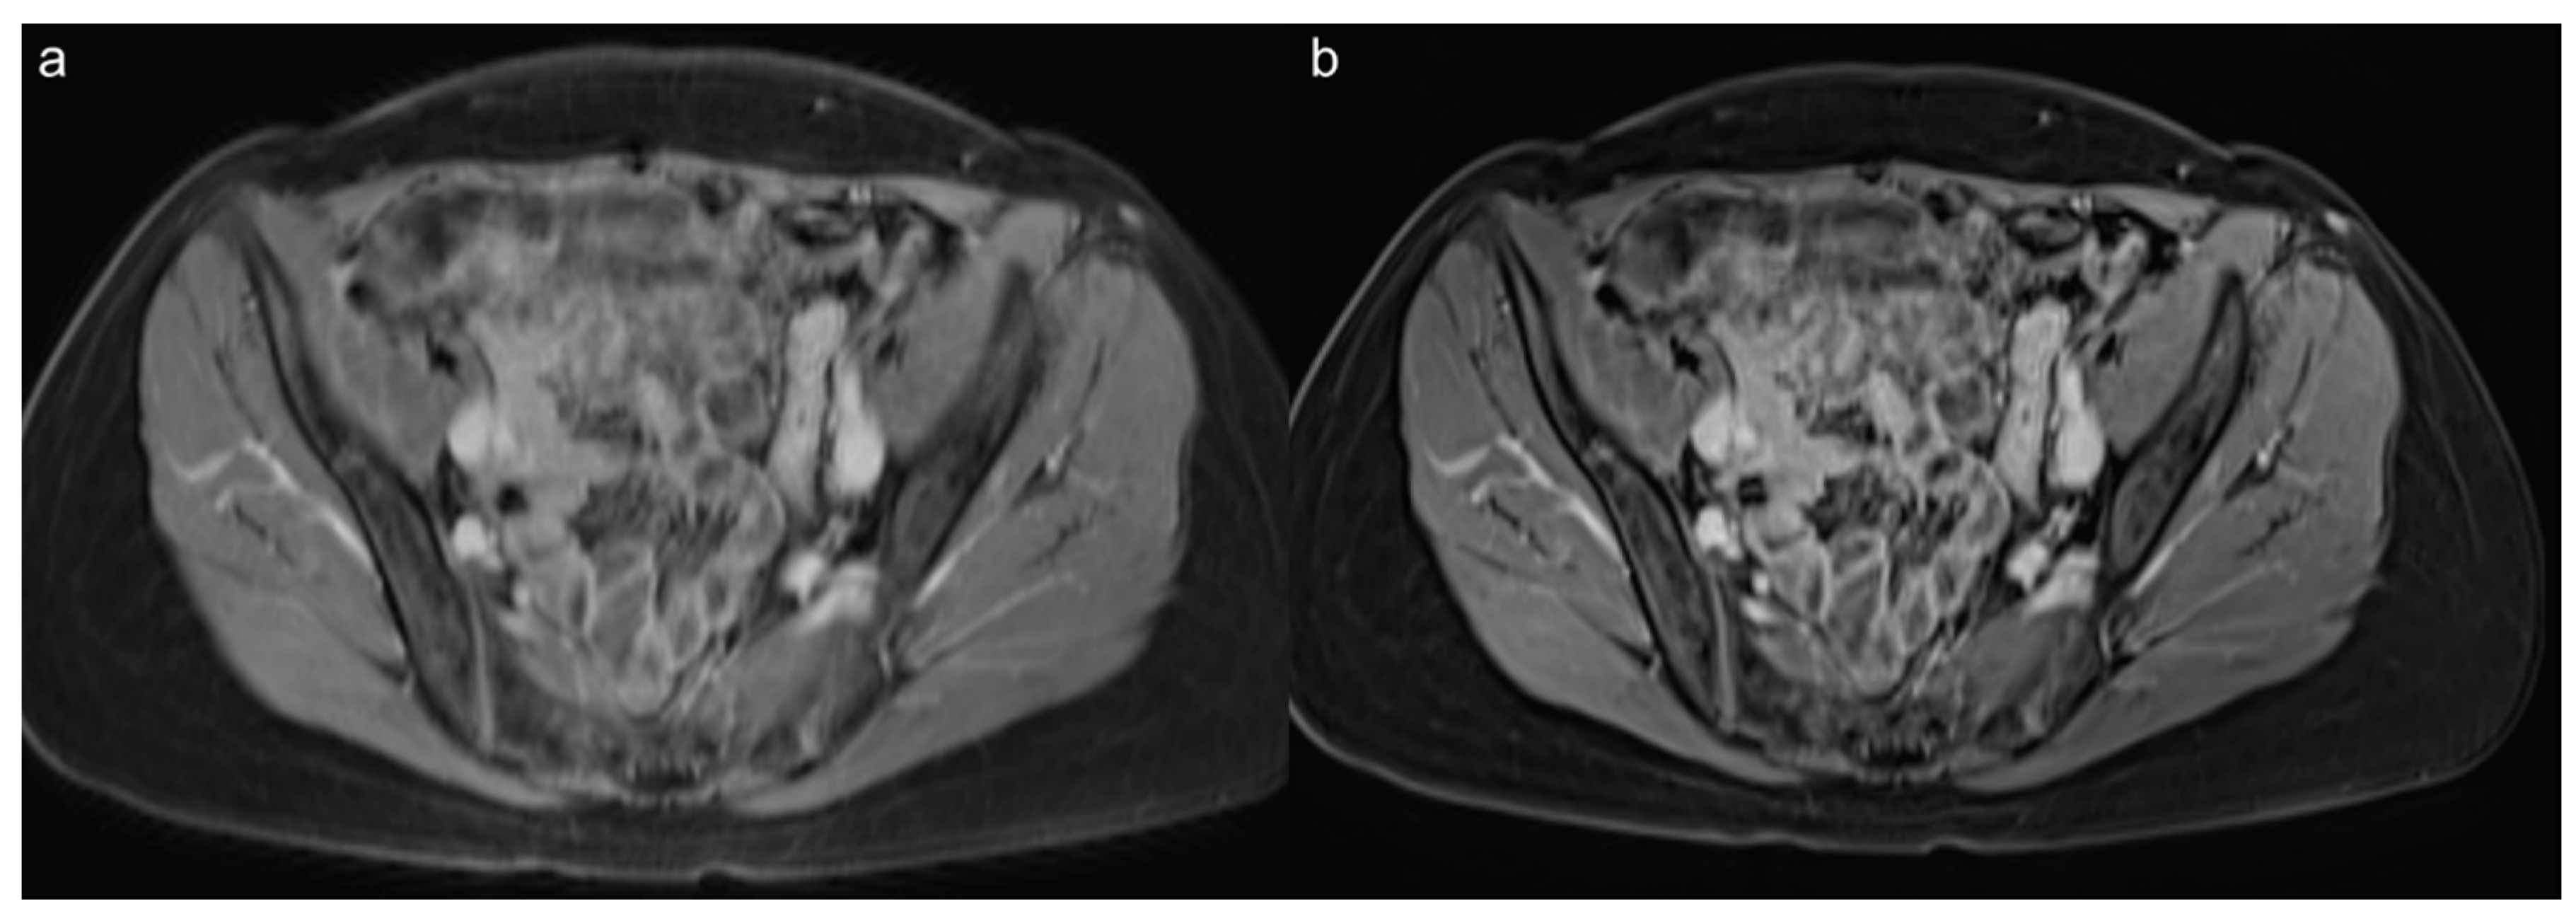

3.3. Qualitative Results of the Precontrast Images

3.4. Qualitative Results of the Postcontrast Images

3.5. Lesion Assessment